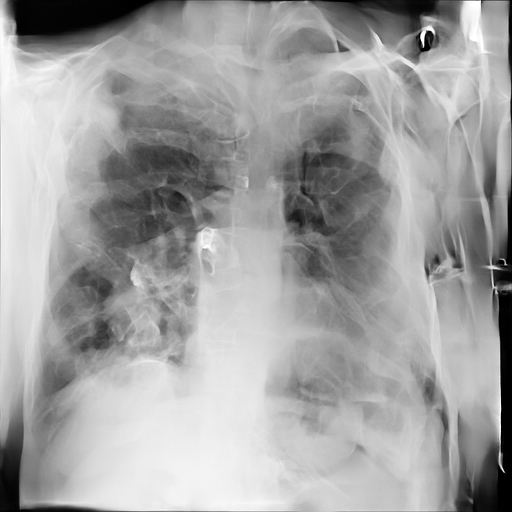

Refer to caption

(a) Original

case 1

(b) ϵ=103HWitalic-ϵsuperscript103𝐻𝑊\epsilon=10^{3}\cdot H\cdot W

(c) ϵ=102HWitalic-ϵsuperscript102𝐻𝑊\epsilon=10^{2}\cdot H\cdot W

(d) ϵ=101HWitalic-ϵsuperscript101𝐻𝑊\epsilon=10^{1}\cdot H\cdot W

(e) Original

case 2

(f) ϵ=103HWitalic-ϵsuperscript103𝐻𝑊\epsilon=10^{3}\cdot H\cdot W

(g) ϵ=102HWitalic-ϵsuperscript102𝐻𝑊\epsilon=10^{2}\cdot H\cdot W

(h) ϵ=101HWitalic-ϵsuperscript101𝐻𝑊\epsilon=10^{1}\cdot H\cdot W

(i) Original

case 3

(j) ϵ=103HWitalic-ϵsuperscript103𝐻𝑊\epsilon=10^{3}\cdot H\cdot W

(k) ϵ=102HWitalic-ϵsuperscript102𝐻𝑊\epsilon=10^{2}\cdot H\cdot W

(l) ϵ=101HWitalic-ϵsuperscript101𝐻𝑊\epsilon=10^{1}\cdot H\cdot W

(m) Original

case 4

(n) ϵ=103HWitalic-ϵsuperscript103𝐻𝑊\epsilon=10^{3}\cdot H\cdot W

(o) ϵ=102HWitalic-ϵsuperscript102𝐻𝑊\epsilon=10^{2}\cdot H\cdot W

(p) ϵ=101HWitalic-ϵsuperscript101𝐻𝑊\epsilon=10^{1}\cdot H\cdot W

Figure 2: ϵitalic-ϵ\epsilon-LDP-processed CXR images obtained with DP-GLOW.

In Fig. 1, we show four ϵitalic-ϵ\epsilon-LDP-processed CXR images of clinical cases obtained with the image domain LDP, which directly imposes the Laplace mechanism on the input image, with different privacy budgets together with the original images. Fig. 2 shows four ϵitalic-ϵ\epsilon-LDP-processed CXR images of clinical cases obtained with DP-GLOW and different privacy budgets together with the original images. In case 1 for DP-GLOW, there is decreased permeability in the bilateral hilar regions. Although this hilar opacity tends to be preserved with a larger privacy budget, the entire image is degraded when the privacy budget becomes 101HWsuperscript101𝐻𝑊10^{1}\cdot H\cdot W. A similar tendency is observed in the images of all the four cases for DP-GLOW; for example, in case 4 with ϵ=101HWitalic-ϵsuperscript101𝐻𝑊\epsilon=10^{1}\cdot H\cdot W, the lung opacity suggesting pneumonia in the right lower lung field is well preserved, while the entire image is degraded.